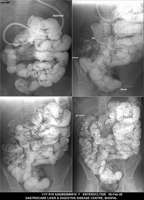

Section: ENTEROCLYSIS

Total: 205 Cases